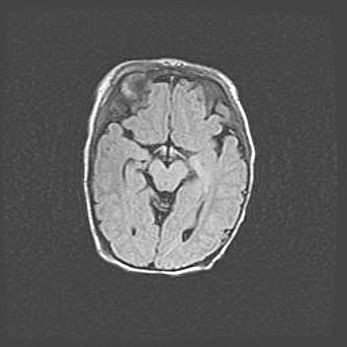

Сообщающаяся гидроцефалия. Кистозная энцефаломаляция головного мозга.

Возраст: 3 месяца 4 дня

Вес: 3100 г

Пол: женский

Окружность головы: 34 см

Срок гестации: 31 неделя

Кистозная энцефаломаляция головного мозга - одна из форм поражения головного мозга в детском возрасте. Характеризуется возникновением множественных и распространённых кист в коре, белом веществе и подкорковых образованиях головного мозга у плодов, новорождённых и детей раннего возраста. Развитие кистозной энцефаломаляции связано с внутриутробной асфиксией и гипотонией, родовой травмой, тромбозом синусов, пороками развития сосудов, инфекциями, сепсисом и другими причинами. Наиболее значимые инфекционные агенты: вирусы простого герпеса, цитомегалии, краснухи, токсоплазмы, энтеробактерии, золотистый стафилококк и другие.